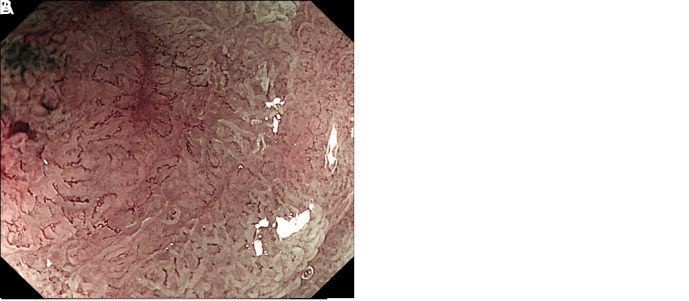

A Rare Case of Early Gastric Mixed Neuroendocrine-Non-Neuroendocrine Neoplasm.

早期胃神经内分泌-非神经内分泌混合性肿瘤1例。